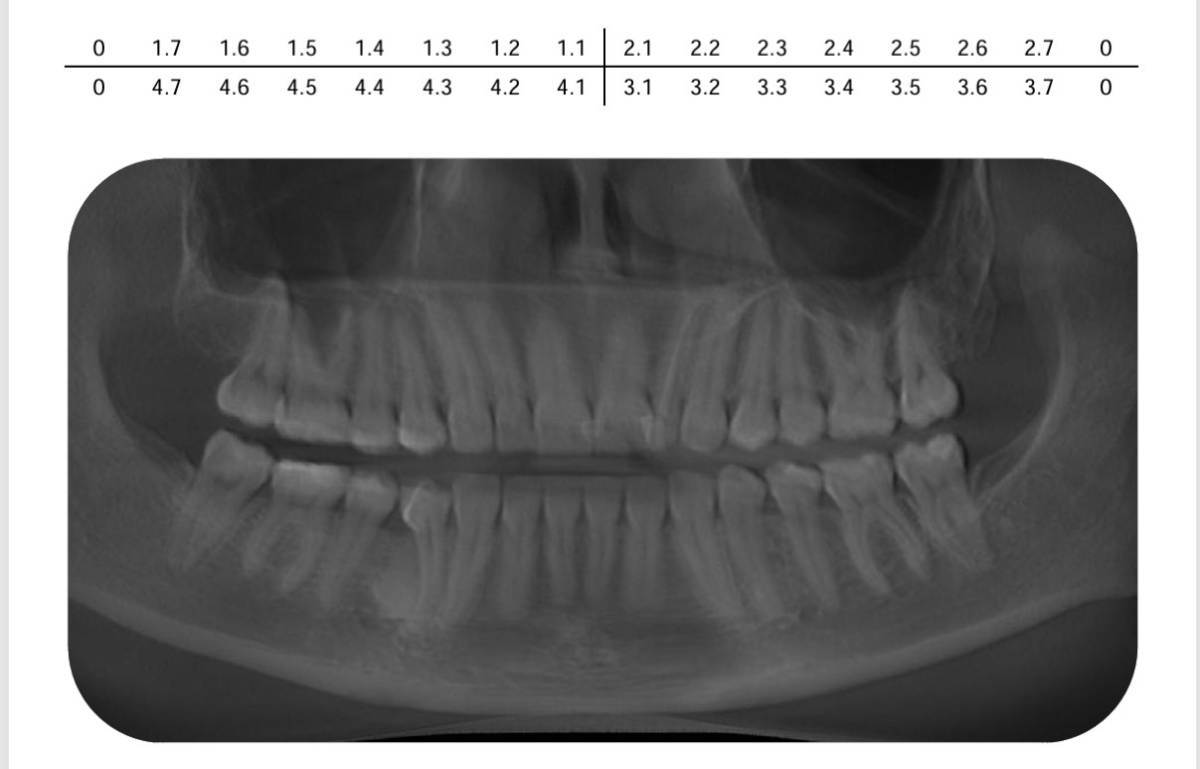

leviosa Опубликовано 8 часов назад Поделиться Опубликовано 8 часов назад Добрый день, уважаемые форумчане. Решила я исправлять прикус, т.к. есть нарушение смыкания зубов, с правой стороны жевать не особо удобно, слева нормально. Плюс скученность. Ортодонт, увидев мою КТ, отказался брать меня на лечение, т.к. его смутило это: в межкорневой области 44-45 определяется участок уплотнения костной ткани с ровным, четким контуром размером 12.2х9.3х6.5 мм. Сказал, что зубы не подвинутся, ну или чего похуже может быть. Удаляйте 44 зуб с этим костным участком, ставьте имплант и приходите, с остальным проблем не видит. А мне жаль удалять живой зуб, с имплантами дел не имела, все зубы свои. Я хотела исправить в том числе и положение 44 зуба, чтобы не было десневого кармана, ведь там постоянно воспаляется десна. Буду благодарна за дельный совет, может кто сталкивался с таким. Прикрепила снимки годовой давности, т.к. новая КТ у меня без расшифровки. В Ez3D Plus не разбираюсь, чтобы нормально заскринить. Из совсем недавних изменений - пломбу 44 зуба переделали, врач хотела убрать нависающий край и применить другую матрицу, но это не помогло; десна все равно не прикрепляется к зубу нормально и часто ноет). Ссылка на комментарий